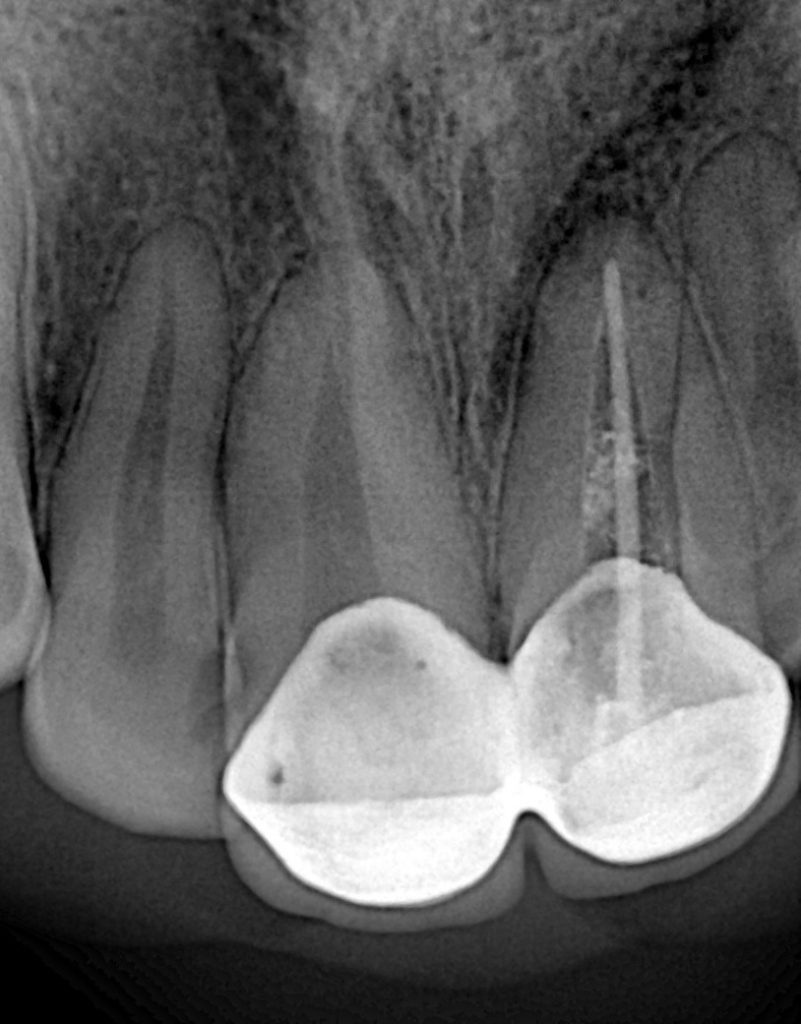

Step 1 — Endodontic Management

Root canal therapy was performed on both centrals due to pulpal exposure and chronic symptoms.

Protocol included:

- Full rubber dam isolation

- Chemomechanical preparation with NaOCl + EDTA

- Shaping with controlled torque instrumentation

- Warm vertical obturation for dense apical seal

- Post-endo coronal build-up for crown retention

This provided a stable biological foundation before prosthetic steps.